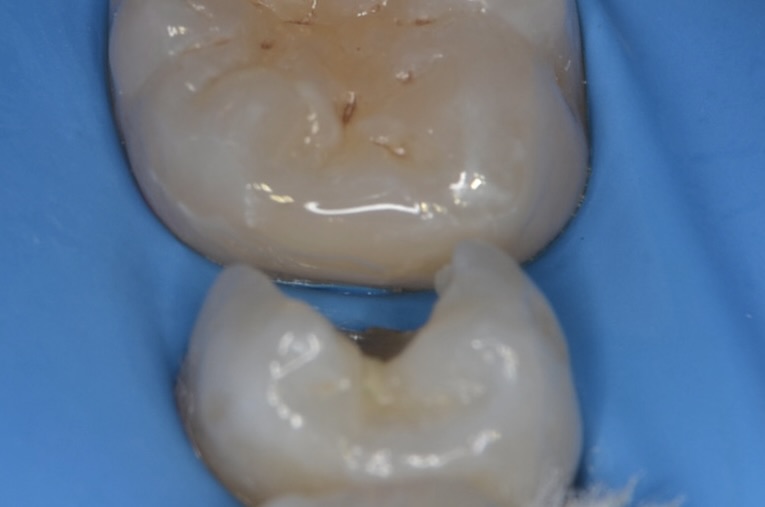

5番虫歯除去

青い齲蝕検知液で虫歯を染めて染まった部分を削ります。この工程を青く染まらなくなるまで歯にできるだけダメージがないように優しい力で丁寧に行います。この作業は時間がかかります。保険診療の短い時間で行うことは限界があります。 -

露髄

虫歯を完全に取り除くと出血してきました。 -